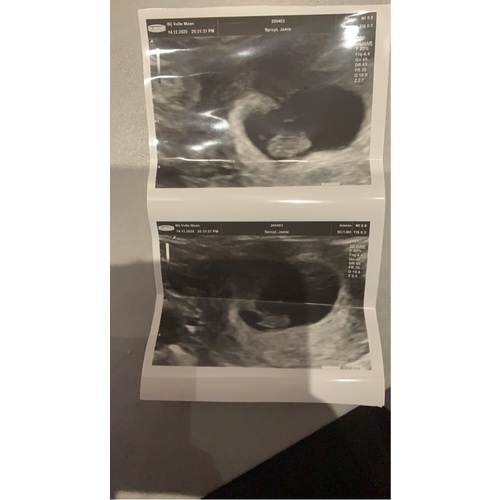

Ik dacht 8 weken te zijn bij de echo ze hadden me alleen iets terug gezet naar 7+4. Nu alweer een goede termijn echo gehad en vandaag alweer 11+4.

Helaas moeilijk tezien gisteren echo gehad ban 8+5 maar mijn baarmoeder ligt nog wat verder naar achter dus niet zn hele helderen echo maar hartje klopt en alles was goed 😍😍